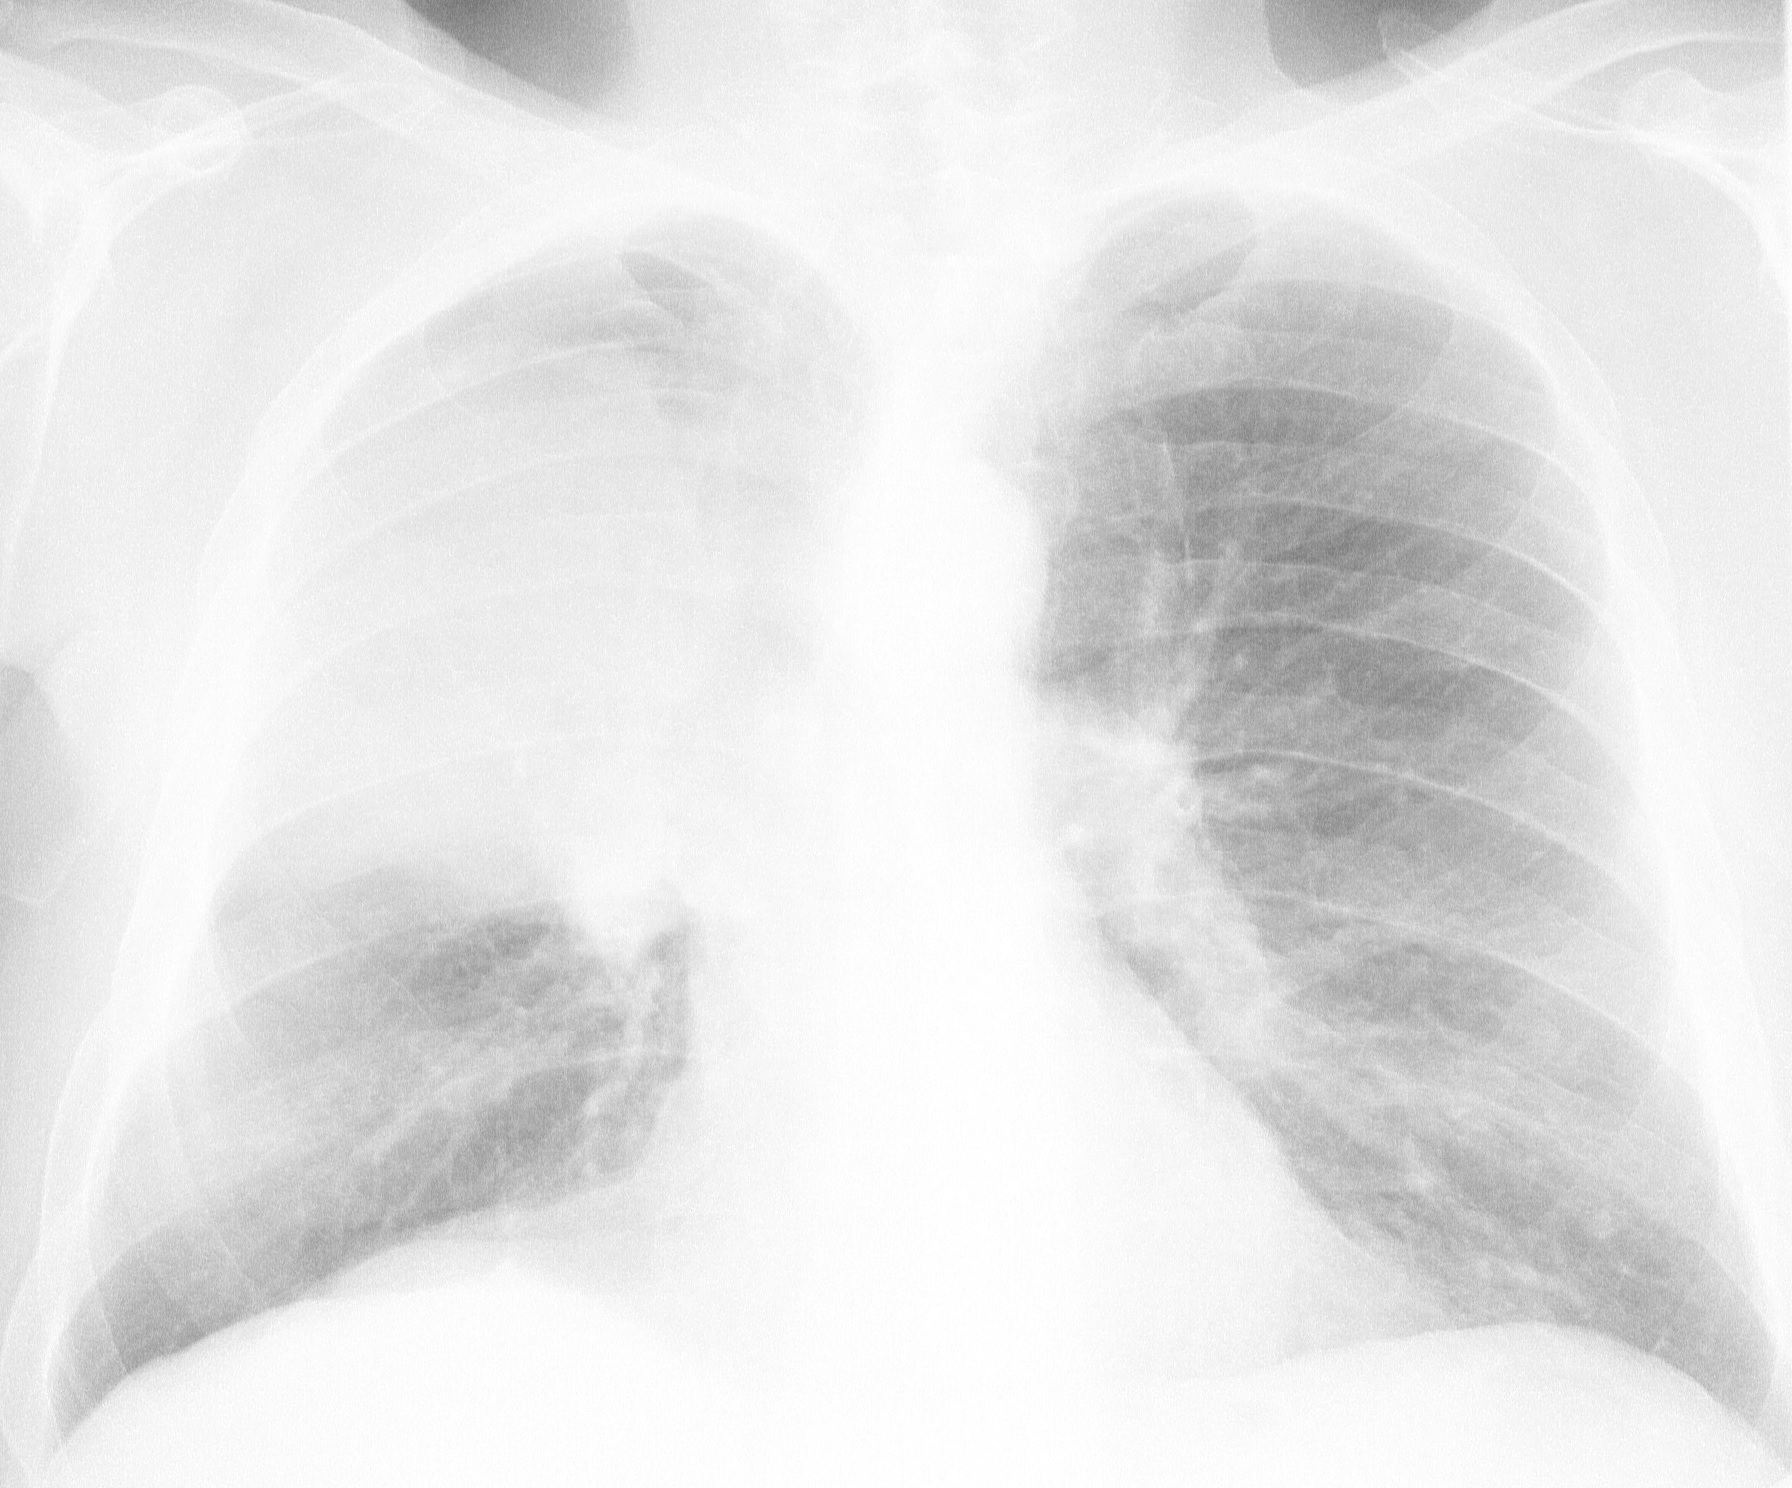

101. ФЛГ

Мужчина 70 лет. Проф. Флг. Справа в в\д инфильтрация, ателектаз? Сейчас информации нет, как придет, доснимем правый бок и будет больше информации . Ваше мнение коллеги? Архива нет. Приехал с другого...

Тип: Клиническое наблюдение

Область: Грудная клетка и верхние дыхательные пути

Модальность: Rg

Дата: 09.11.2018 - 22:04